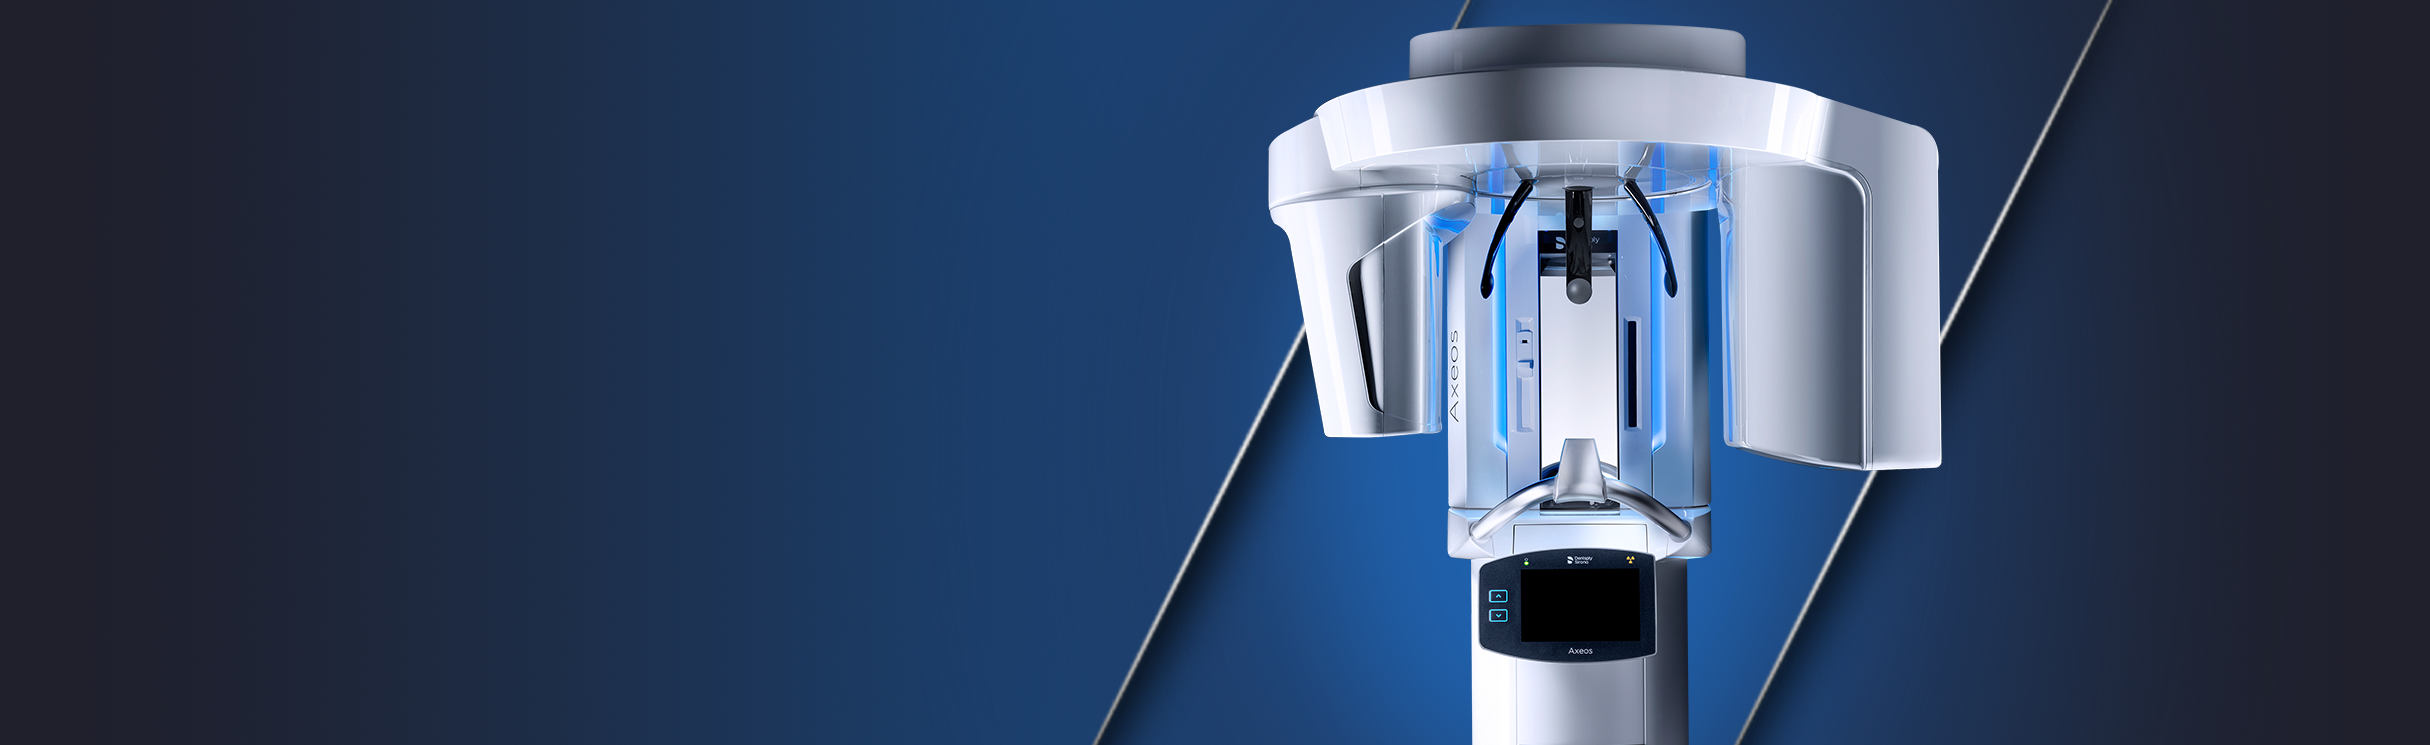

Trate a los pacientes con más confianza con las máquinas CBCT

La máquina de tomografía computarizada de haz cónico permite a los profesionales dentales ver, diagnosticar y tratar a los pacientes con mayor confianza gracias a las radiografías 3D que produce el haz cónico dental.

Dentsply Sirona ofrece máquinas de tomografía dental innovadoras y brinda calidad y facilidad de uso a esta máquina de radiología dental, lo que resulta en excelencia clínica, satisfacción del paciente y mayor rentabilidad.